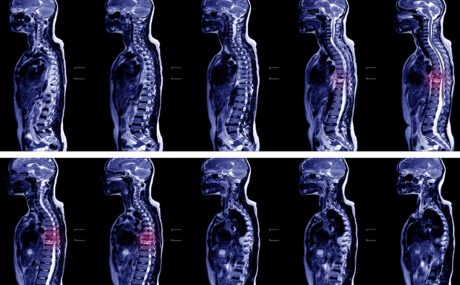

An urgent MRI scan was requested by the A&E doctors but refused by the radiology team who failed to recognise that this was an emergency situation. They instead scheduled XX for a less urgent slot the following morning. There were other patients with less urgent scans that were scanned and her scan was not prioritised appropriately. At the scan the following morning an abscess was discovered in her cervical spine.